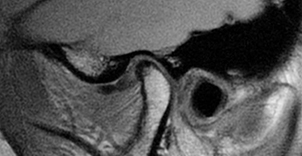

Blood investigations are only helpful if systemic diseases such as rheumatoid arthritis, temporal arteritis or connective tissue diseases are suspected. Plain radiography is useful as a screening tool for bony involvement, but not for disc disorders. Ultrasound imaging is helpful but requires skilled interpretation. Disc morphology and displacements are better identified by MRI scanning (Figure 1). Arthrogenous TMD is best investigated by CT scanning, particularly in advanced cases where planning for joint replacement is envisaged. Arthroscopy, as an invasive diagnostic tool, is useful in patients with internal derangements not responding to conservative regimes; and may also be therapeutic by division of adhesions, lavage of the joint and allowing repositioning of a displaced disc.

Figure 1: TMJ MRI scan.